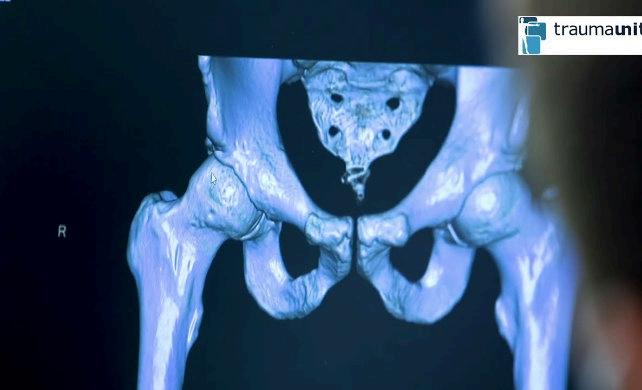

Quizá no lo sabías, pero la traumatología cobra cada vez más importancia en México: en 2019, sólo el IMSS registró 11,615 fracturas de cadera en personas mayores de 65 años, una tasa de 176 fracturas por cada 100,000 derechohabientes. Según la Guía de práctica clínica del IMSS, la probabilidad de sufrir una fractura de cadera a partir de los 50 años es de 8.5% en mujeres y 3.8% en hombres.

No son datos aislados. La traumatología y ortopedia han dejado de ser áreas médicas periféricas: hoy son esenciales para atender una creciente carga de lesiones óseas, traumatismos y padecimientos que afectan a todas las edades.

Por ello, esta especialidad ha evolucionado profundamente, incorporando tecnologías como artroscopias de cadera, cirugía de rodilla con prótesis, microcirugía vertebral, abordajes mínimamente invasivos y neuronavegaciónencolumnas¿Noconocesqué son?Tranquilo, nosotros tampoco, por eso hicimos este especial.

¿CUÁLES SON LAS FRACTURAS MÁS FRECUENTES EN PERSONAS CON OSTEOPOROSIS?

De radio distal (muñeca), de fémur proximal (cadera), de vértebras lumbares o torácicas